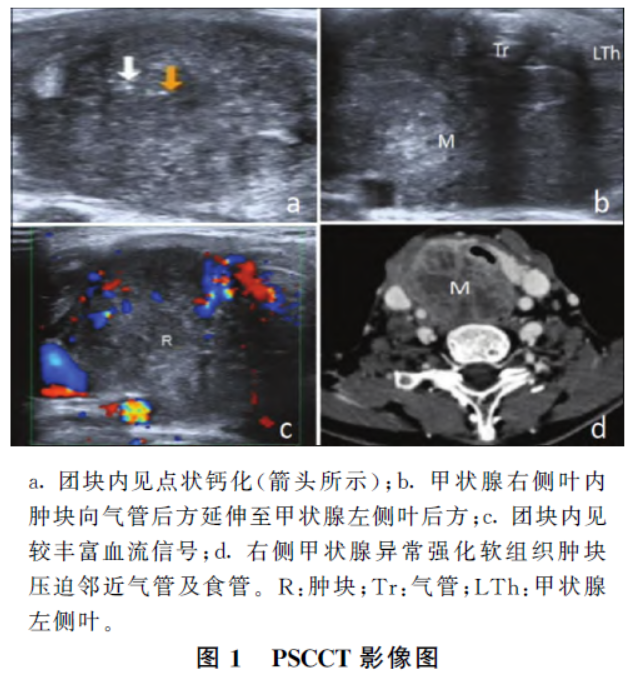

超声检查:甲状腺右侧叶探及一个实性低回声团块,大小约56mm×55mm×34mm,边界不清,形态不规则,内部回声欠均匀,可见微小点状钙化(图1a);团块与气管分界不清,向气管后方延伸至甲状腺左侧叶后方(图1b),气管及食管受压明显,彩色多普勒血流成像(color Doppler flow imaging,CDFI)于团块内探及较丰富血流信号(图1c)。

颈部CT 检查提示:右侧颈根部异常强化软组织肿块(图1d),考虑甲状腺右侧叶肿瘤性病变,甲状腺癌可能,压迫邻近气管及食管;双侧颈根部、颈动脉鞘旁多发肿大淋巴结。术中所见:右侧甲状腺内触及一大小约5cm×4cm×3cm 的质硬肿块,肿块于右侧喉返神经入喉处突破甲状腺外膜,向气管后方延伸至左侧甲状腺后方。